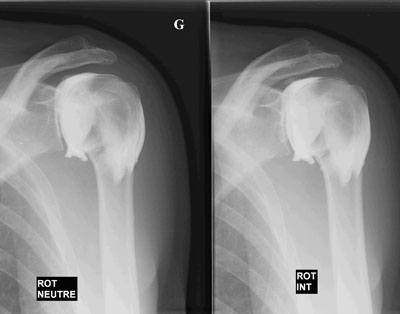

Epaule

Arthrographie de l'épaule

Capsulite rétractile arthrographie (images 1 et 2)

Arthroscanner correspondant (images 3 et 4)